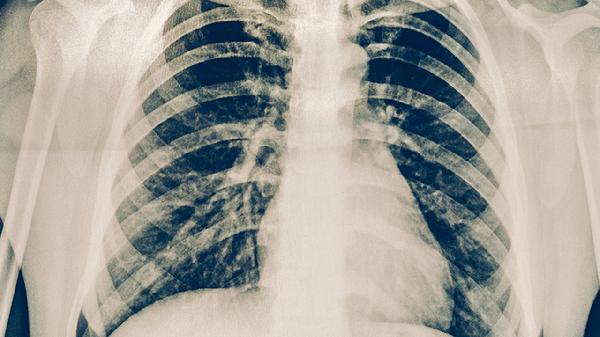

成人肺炎的注意事项有哪些

成人肺炎的注意事项主要有保持充足休息、遵医嘱规范用药、监测症状变化、加强营养支持、预防交叉感染。